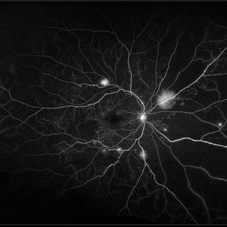

Central Retinal Vein Occlusion with Severe Ischemia

Composite fluorescein angiogram of the left eye of a male with a Central Retinal Vein Occlusion with severe ischemia.

Photographer: Olivia Rainey

Imaging device: Heidelberg Spectralis

Condition/keywords: central retinal vein occlusion (CRVO), composite, fluorescein leakage, ischemic CRVO